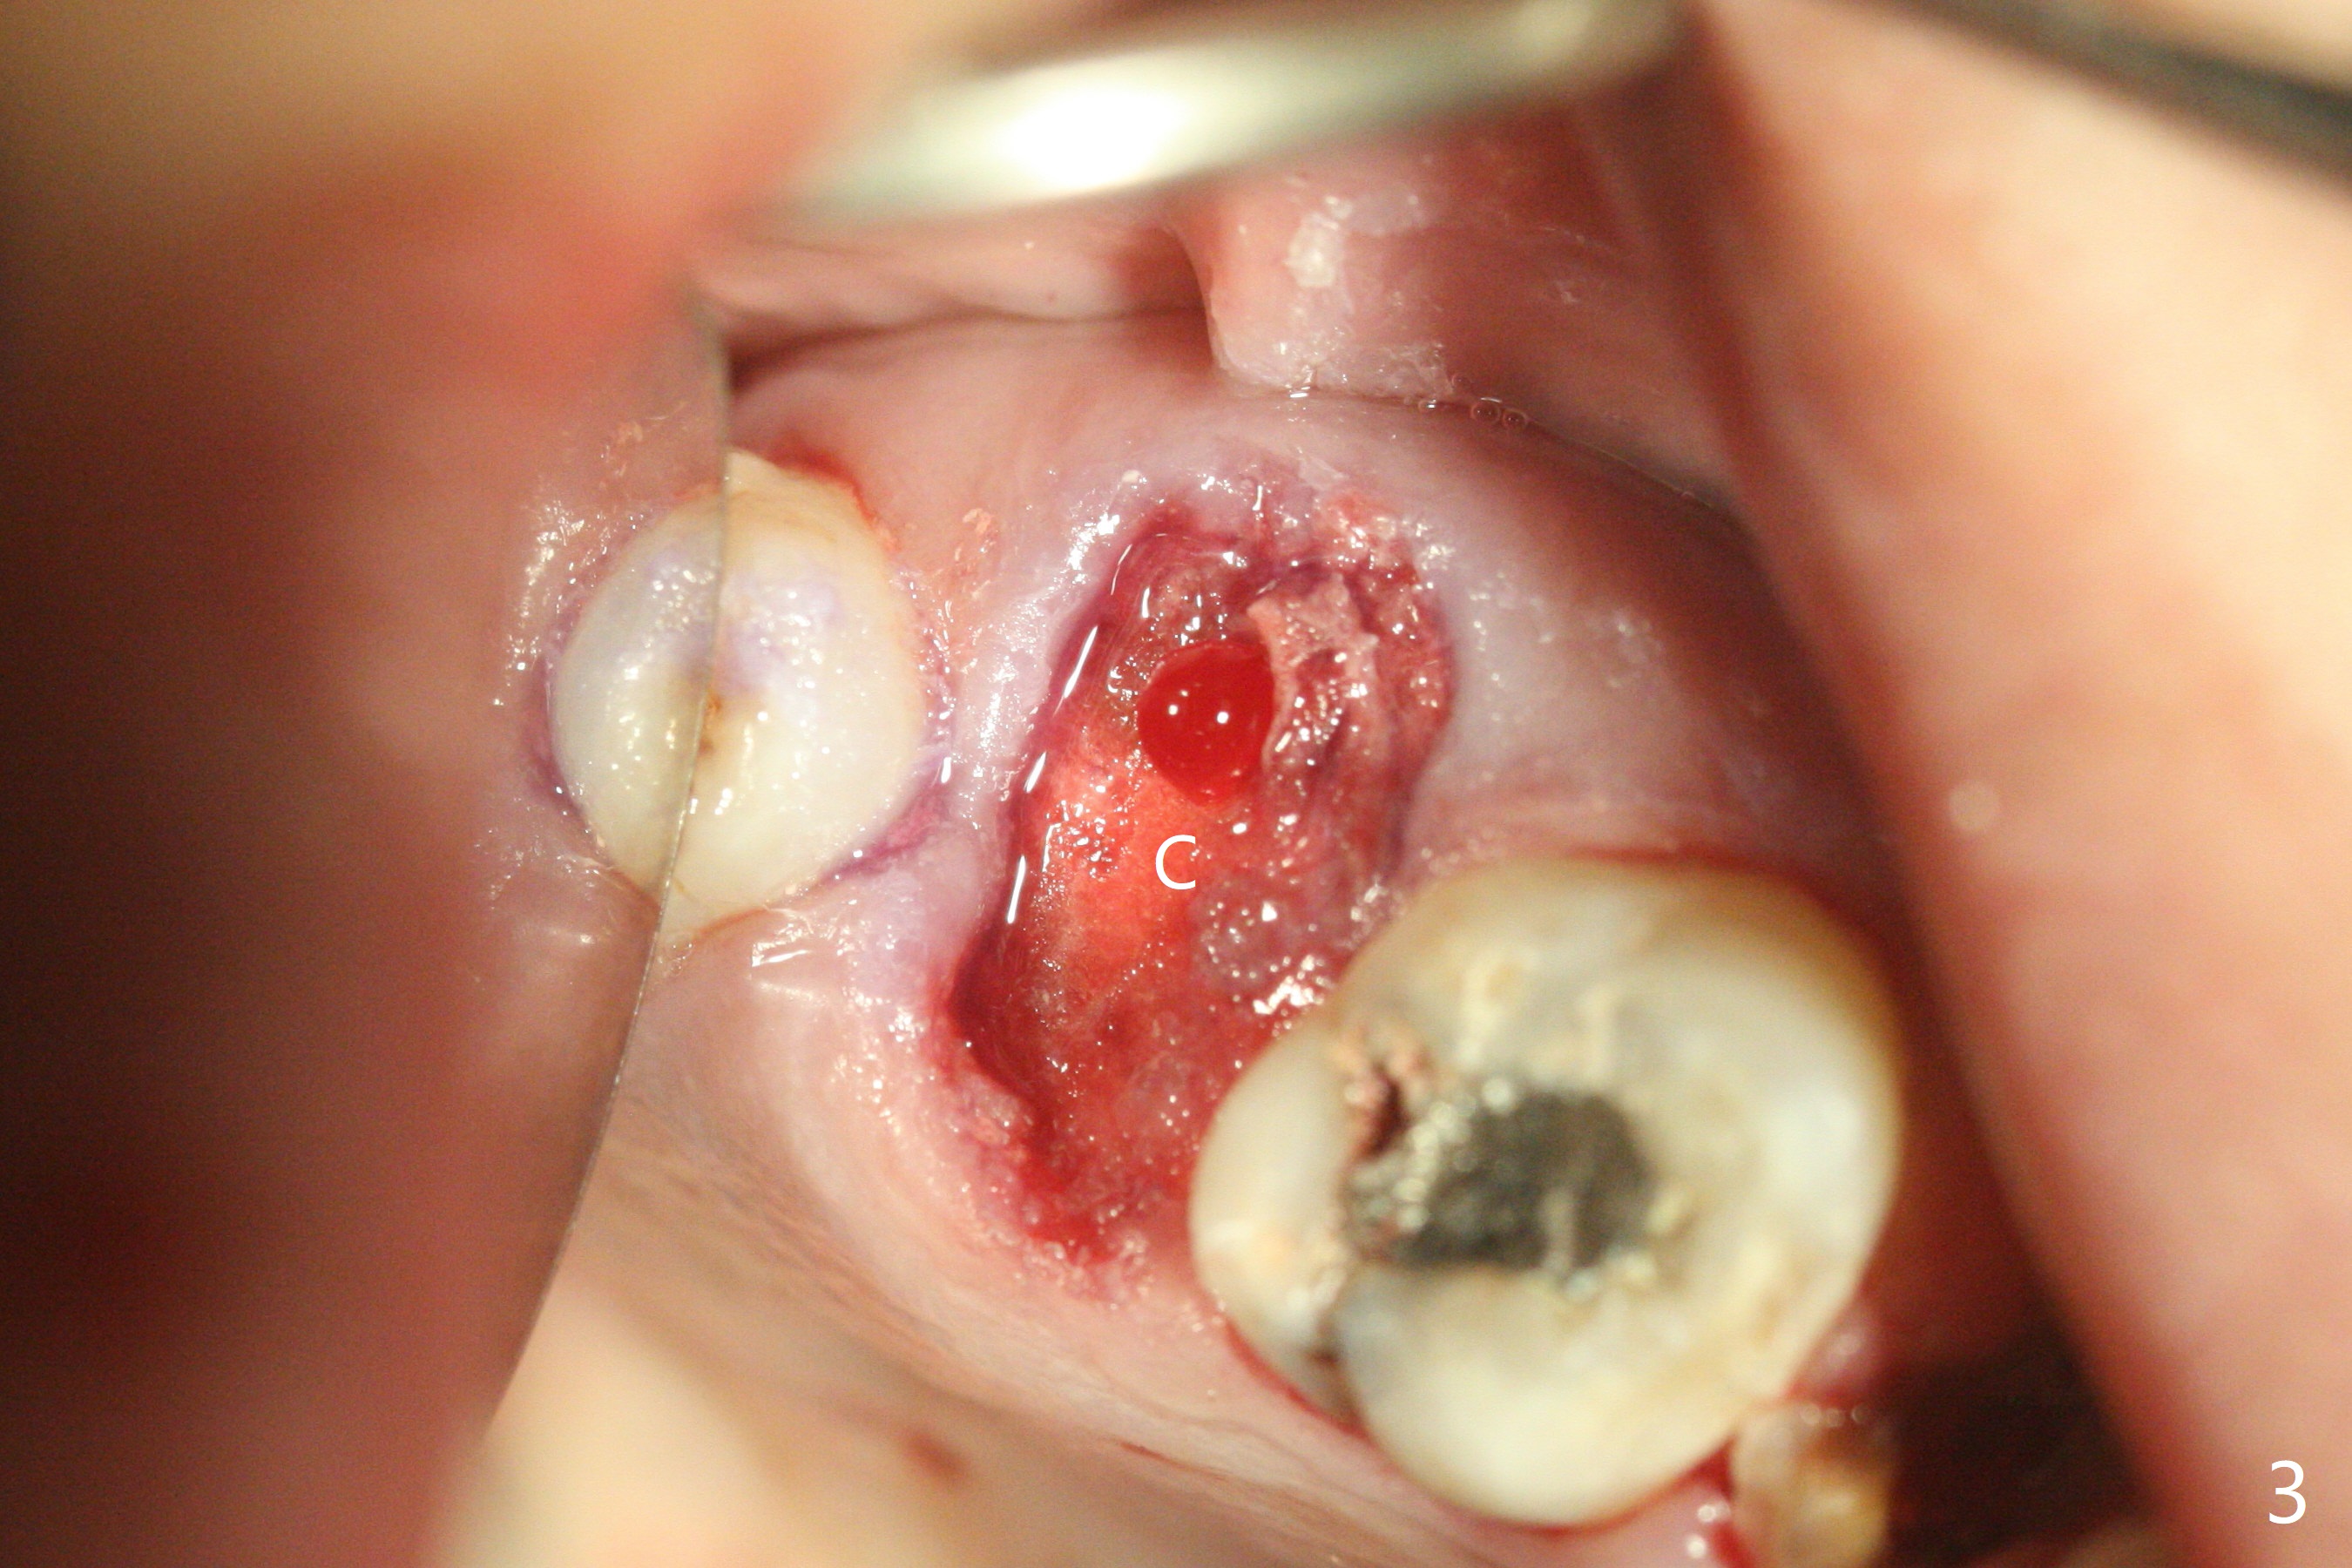

38岁女,牙列不全,咬合塌陷,因右上7疼痛就诊(图一),十分恐惧治疗,虽然残根好像不大,骨粉填入不少(图二:*;使用.5毫升GEM21S,异体骨和合成材料(ß-TCP (beta tricalcium phosphate)),使用不带齿刮匙或者充填器压入牙槽窝。使用GEM Cap(9-12月吸收膜)关闭牙槽窝开口(图三:C),牙周胶水固定膜。由于右下7延申(图一(箭头),四),没有空间放置牙周或者树脂敷料。膜术后4天脱落(加用缝线可以避免早期脱落),7天伤口明显缩小(膜早期脱落好处,图五,与图三对比),白色的骨粉仿佛稳定,所以没有做特殊处理,观察。No Caries GEM21S Xin Wei, DDS, PhD, MS 1st edition 01/26/2021, last revision 02/01/2021